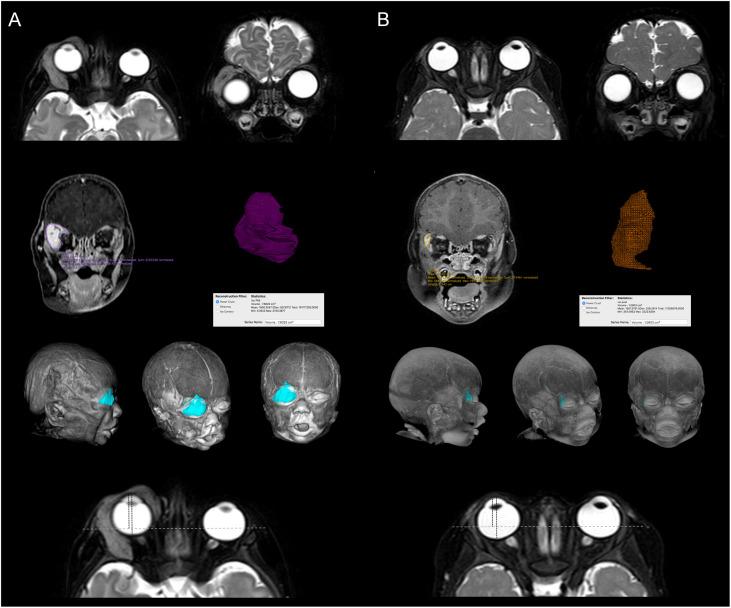

retrospective observational cohort study. Propranolol was administered at an initial oral dose of 1 mg/kg and subsequently increased to 2 mg/kg for 1 year. Outcomes were evaluated by comparing pre- and post-treatment clinical findings, contrast-enhanced ultrasound (CEUS) findings and/or orbital magnetic resonance imaging findings from baseline to 3, 6, 9, 12, 24, and 48 weeks. Regression was graded as follows: satisfactory when 90% and above of the baseline lesion volume and extension decreased, acceptable when 50 to 90%, mediocre when 30 to 50%, poor less than 30%.

回顾性观察队列研究。普萘洛尔初始口服剂量为1mg/kg,随后增至2mg/kg,持续1年。通过比较治疗前和治疗后从基线至3、6、9、12、24和48周的临床检查结果、超声造影(CEUS)结果和/或眼眶磁共振成像结果来评估疗效。消退分级如下:基线病变体积和范围减少90%及以上为满意,减少50%至90%为可接受,减少30%至50%为中等,减少不足30%为差。